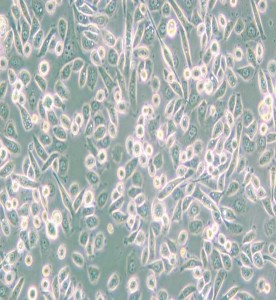

PC-9人肺癌細(xì)胞

中文名稱 :人肺癌細(xì)胞

細(xì)胞簡(jiǎn)稱 :PC -9

細(xì)胞形態(tài) :圓形/上皮細(xì)胞樣

生長(zhǎng)特性 :半貼半懸